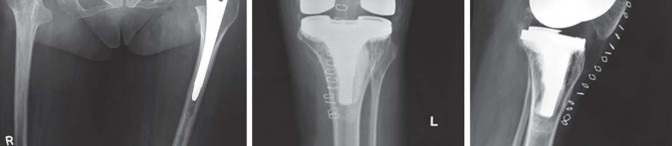

يميل مرضى التهاب المفاصل الروماتويدي اليفعي إلى امتلاك قناة نخاعية فخذية ضيقة جدًا مع عدم توافق بين قطر القناة القريبة والبعيدة. يمكن أن يختلف التجويف الحقي من النوع المشوه (كما يظهر في الشكل 29.1) إلى النوع المنغمس (كما يظهر في الشكل 29.2) أو قد يكون مفصل ورك ملتحم (كما يظهر في الشكل 29.3).

انصهار ثنائي في مفصل الورك بالتهاب المفاصل اليفعي